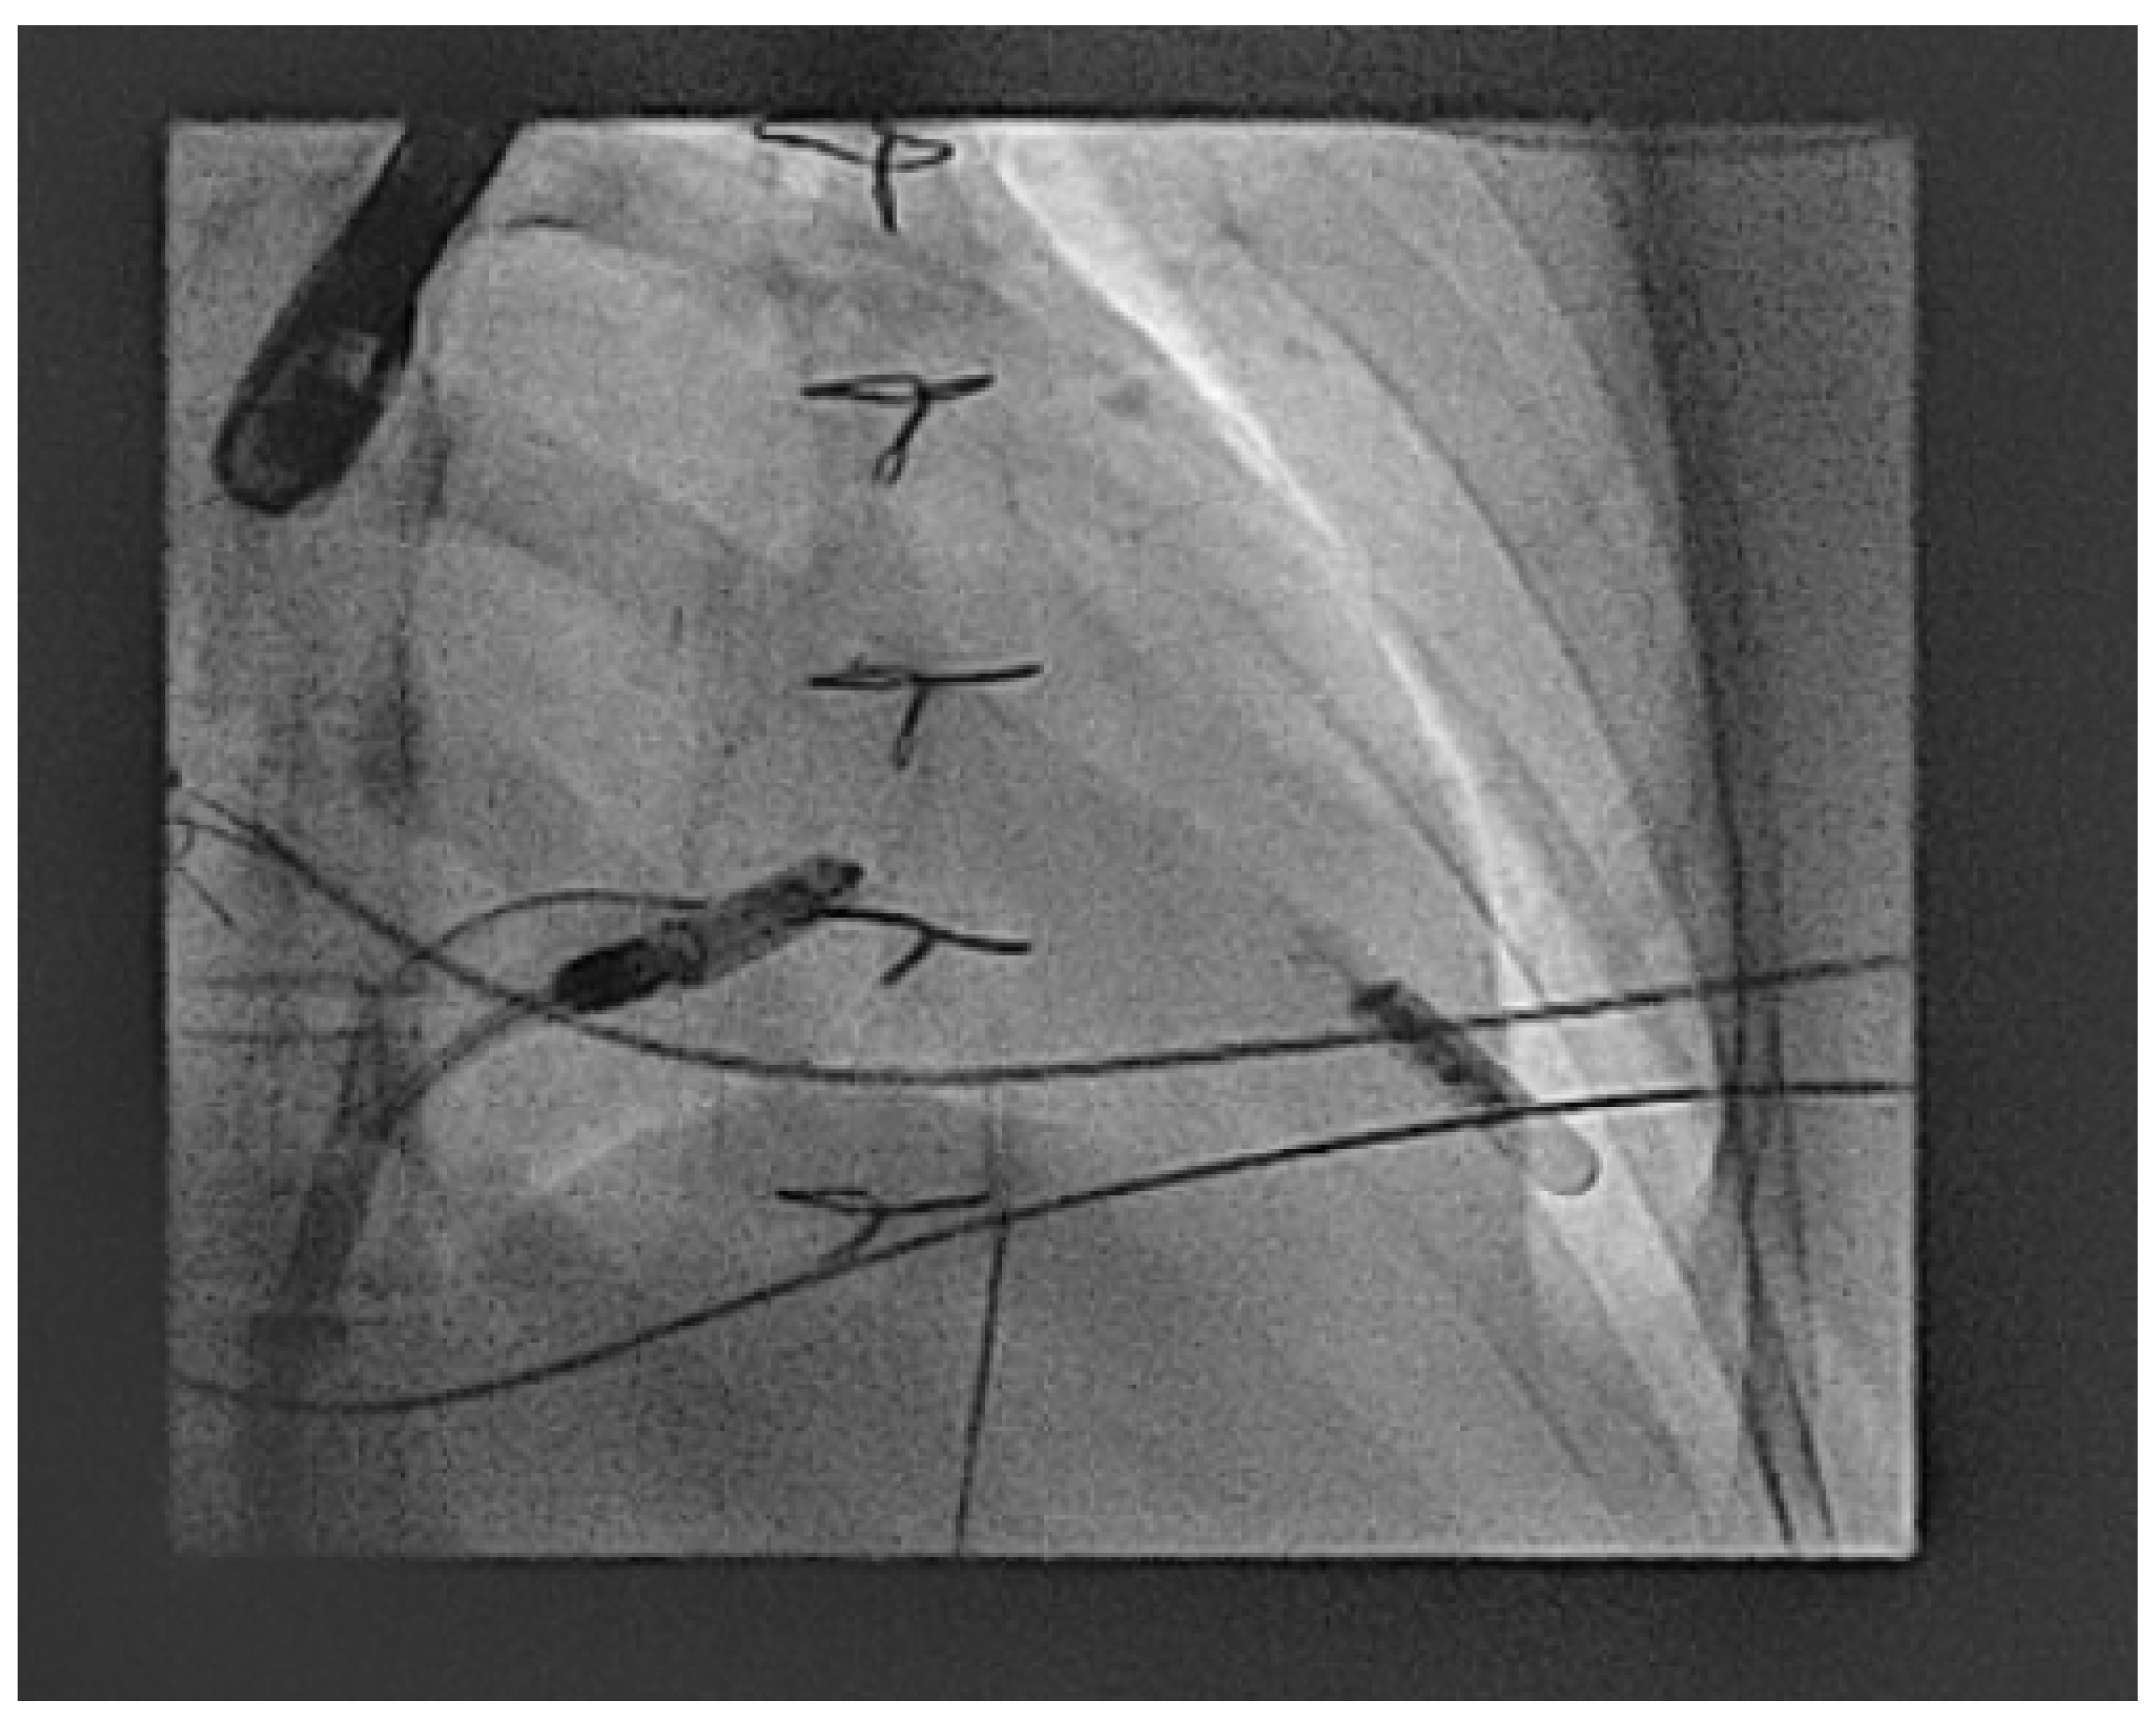

- Hayle, P.; Altayeb, F.; Hale, A.; Rao, A.; Ashrafi, R. Case report demonstrating novel approaches for leadless pacemaker implantation in the single ventricle heart. Eur. Heart J. Case Rep. 2025, 9, ytaf146. [Google Scholar] [CrossRef]

- Goulden, C.J.; Khanra, D.; Llewellyn, J.; Rao, A.; Evans, A.; Ashrafi, R. Novel approaches for leadless pacemaker implantation in the extra-cardiac Fontan cohort: Options to avoid leaded systems or epicardial pacing. J. Cardiovasc. Electrophysiol. 2023, 34, 2386–2392. [Google Scholar] [CrossRef]